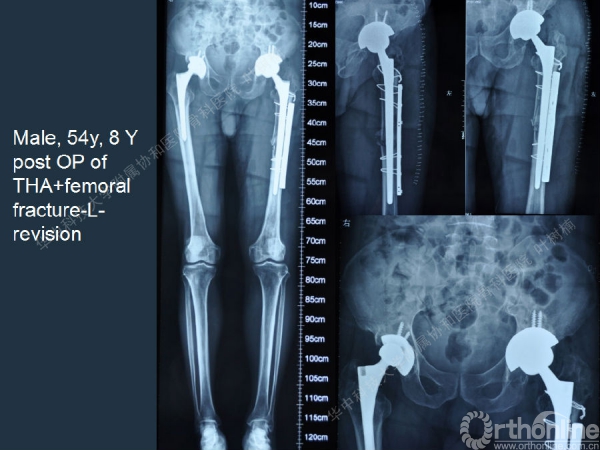

股骨侧翻修